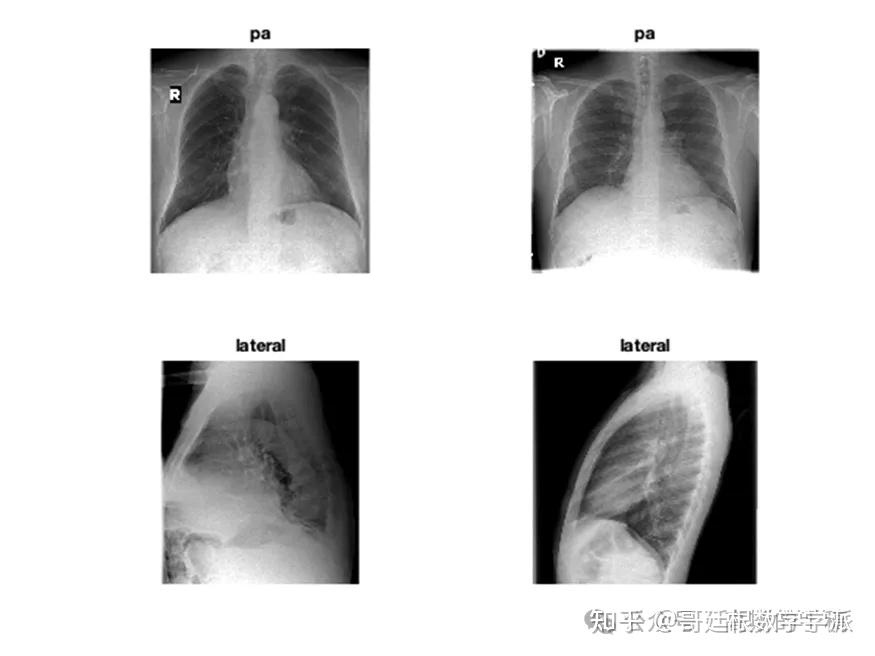

医学图像的深度学习可解释性(MATLAB R2021B)